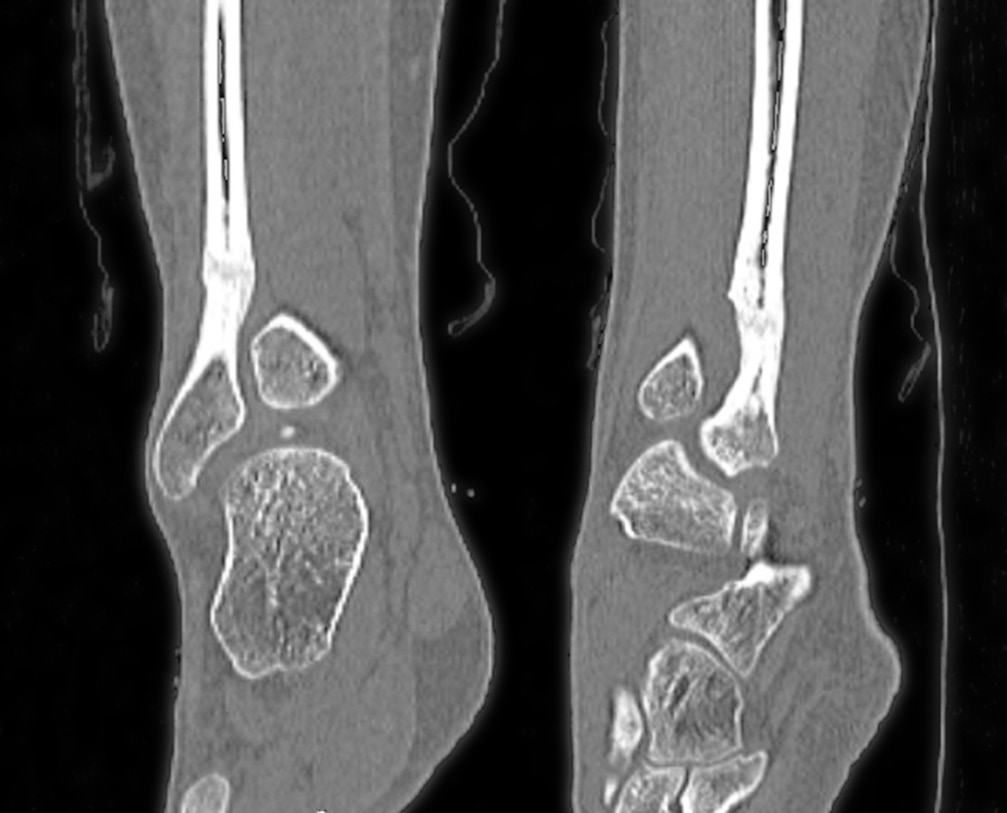

При компьютерной томографии на уровне дистального метадиафиза правой малоберцовой кости определялись деформация, остеосклеротические изменения кости на протяжении 29,0 мм с эндостально расположенными участками высокой плотности; кость локально несколько вздута, отмечались сквозные каналы после туннелизации; узурация и кистовидная перестройка задненаружной поверхности правой таранной кости, утолщение прилежащих отделов суставной капсулы правого голеностопного сустава в задненаружных отделах вследствие незначительного отека, количество синовиальной жидкости было несколько увеличено (рис. 4).

Рис. 4. Мультиспиральная компьютерная томография. Деформация, остеосклеротические изменения кости на протяжении 29,0 мм с эндостально расположенными участками высокой плотности; кость локально несколько вздута

11.04.2017 из-за неэффективности консервативного и оперативного лечения проведена субпериостальная сегментарная резекция склерозированного участка нижней трети правой малоберцовой кости в пределах неизмененной костной ткани. Размеры резецированного участка кости составили 1,5 × 3,0 см. По гистологическим данным определен участок остеосклероза. Наложена гипсовая лонгета сроком на 8 нед. (рис. 5).

Рис. 5. Рентгенограмма. Состояние через месяц после операции — сегментарной резекции склеротически измененного участка нижней трети малоберцовой кости

В послеоперационном периоде выраженность болевого синдрома снизилась (до 4–6 баллов по ВАШ). Проводили интенсивные реабилитационные мероприятия. Спустя 4 мес. после резекции склерозированного участка нижней трети малоберцовой кости на контрольной рентгенограмме определялись неоднородность структуры и нечеткость контуров дистального метадиафиза малоберцовой кости с формированием костной мозоли (рис. 6). Признана целесообразной полная нагрузка на конечность. При осмотре через 6 мес. после операции болевой синдром отсутствовал (по ВАШ 0 баллов), наблюдалась потеря чувствительности в области тыльной поверхности стопы. Последующее обследование через 12 мес. после резекции показало отсутствие болевого синдрома и других клинических проявлений. По данным компьютерной томографии прослеживалась отчетливая тенденция к восстановлению органотипической костной структуры нижней трети малоберцовой кости в зоне оперативного вмешательства (рис. 7).

Рис. 6. Рентгенограмма спустя 4 мес. после операции (сегментарной резекции). Образование костной мозоли, заполнение дефекта кости новообразованной костной тканью

Рис. 7. Мультиспиральная компьютерная томография спустя 12 мес. после операции — сегментарной резекции нижней трети малоберцовой кости. Определяются признаки наметившейся дифференциации костной структуры на кортикальный слой и костномозговую полость